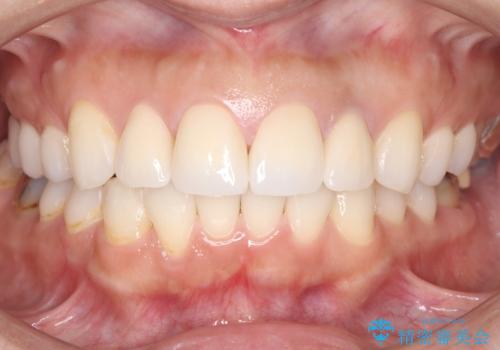

緻密な色合わせと形態調整を重ねた結果、長年のコンプレックスであった前歯の欠けや変色が解消。機能性と審美性が完璧に調和した、自信を持って笑える美しい口元を実現することができました。